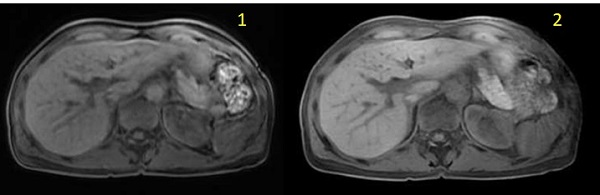

| Number | Description |

|---|---|

| 1 | DISCO free-breathing image |

| 2 | DISCO with Star Imaging Option free-breathing image |